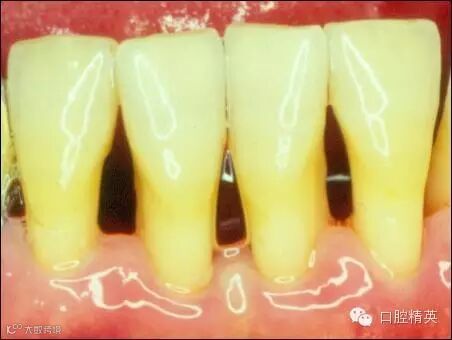

洁完牙后,牙龈组织恢复成粉白色,不再充血发炎